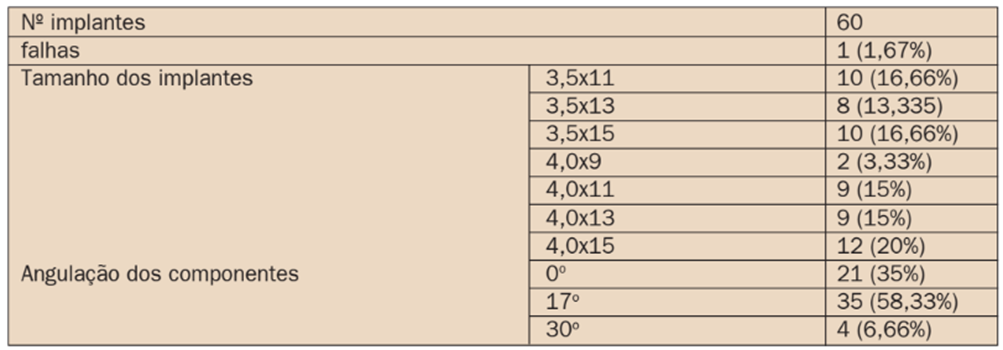

A tabela 2 apresenta os dados referentes aos implantes utilizados e a angulação dos componentes protéticos. Os implantes de 15 mm de comprimento foram os mais utilizados (36,66%), enquanto que implantes de 9 mm foram os menos utilizados, correspondendo a apenas 3,33% das fixações utilizadas. Os componentes de 17º foram os mais utilizados (58,33%), principalmente para corrigir a inclinação dos implantes distais.

Alguns implantes precisaram de implantes de 30º (6,66%) em virtude da maior inclinação dos implantes distais. Os componentes retos foram utilizados nos implantes anteriores. Alguns destes implantes anteriores também precisaram de componentes angulados, muitas vezes em virtude da discrepância entre os maxilares.

TABELA 2: Descrição dos implantes quanto ao tamanho e sobrevivência e dos componentes protéticos quanto a angulação: